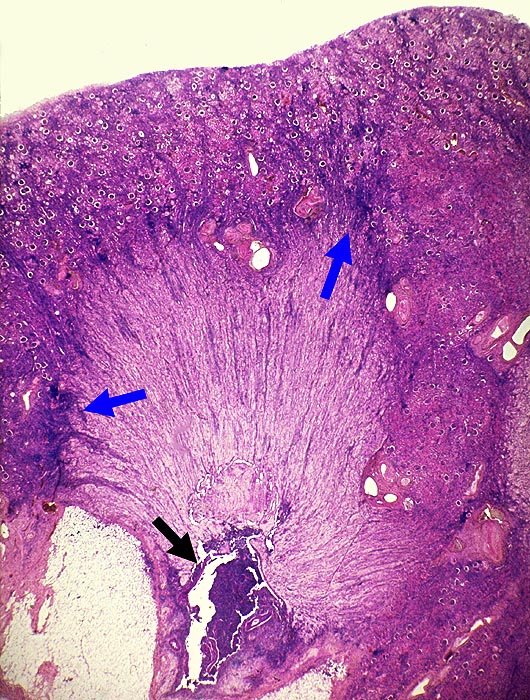

Analgetikanephropathie

Niere, Harnwege

Niere

Pathologischer Befund